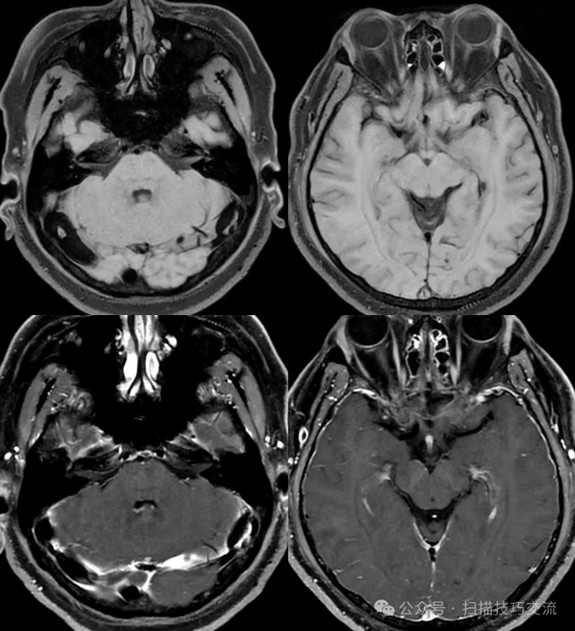

•汗腺分泌:正常,皮肤划痕正常反应。 •尿便障碍:无。性功能障碍无。 •专科情况:正常。不逐一罗列。 •辅助检查:01-05颅脑CT提示:1,上矢状窦、双侧横窦密度较高,请结合临床,必要时进一步检查;2,双侧脑室后角可疑稍高密度影,右顶叶局部脑沟密度可疑增高,建议进一步检查。 •初步诊断:静脉窦血栓

临床申请:颅脑平扫,静脉成像,磁敏感成像,颅内静脉血管黑血成像。

SWAN未见异常。

PC-MRV未见异常。